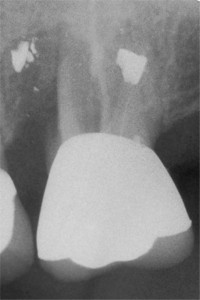

The x-ray above represents a patient who has not visited the dentist for 2 years. The calculus or tartar is now visible on the x-ray as wisps or thorns projecting from the sides of the teeth UNDERNEATH THE GUMS where you can not see them. These 'thorns-of-calculus' are a major cause of puffy and bleeding gums ( gingivitis ) , which leads to bone loss and periodontal disease. Please visit our page on Ultrasonic Cleanings for before and after photos to see how we can make your teeth brighter and squeaky clean once again!